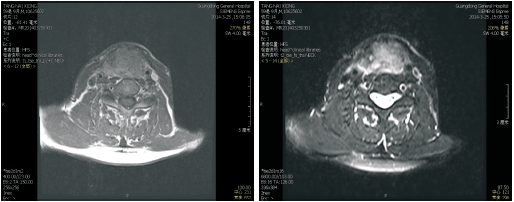

高惠冰:2014年3月患者出现吞咽困难、左耳刺痛、喉部异物感。来院查体: PS评分1分, 颈部见气管造瘘口, 造瘘口右上方可触及肿物。大小约4 cm× 3 cm, 质韧, 活动度差, 无压痛。

2014-03-26喉增强MRI:喉部术后改变, 喉腔内见巨大软组织肿块影, 大小约41 mm× 29 mm, 信号均匀, 边界不清, 增强后病灶明显均匀性强化, 喉腔变窄、消失, 病灶向上累及会厌皱襞, 下缘达甲状腺水平, 见图6和图7, 无病生存期14个月。

诊断:喉鳞状细胞癌术后造瘘口复发rT4aN0M0 Ⅳ A期。